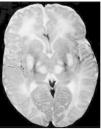

Exploraciones complementarias: hemograma normal; velocidad de sedimentación globular (VSG), 14 mm; bioquímica con normalidad de glucosa, calcio e iones; bilirrubina total, 5,2 mg/dl; bilirrubina directa, 1,1 mg/dl; GOT, 100 U/l; fosfatasa alcalina, 993 U/l, lactato deshidrogenasa (LDH), 708 U/l. Equilibrio acidobásico: pH, 7,33; presión parcial de dióxido de carbono (pCO2), 57; y de oxígeno (pO2), 50; bicarbonato, 30; exceso de bases, 4. Citoquímica y cultivo de líquido cefalorraquídeo (LCR): negativos. Enolasa neuroespecífica en LCR: 32 μg/ml (aumentada). Proteína básica de mielina en LCR: 0,3 ng/ml (0-1,5 ng/ml). Perfil de aminoácidos en sangre y orina: normales. Ácido láctico, 26,1 mg/dl (3-15 mg/dl), y ácido pirúvico, 1,6 mg/dl (0,3-1 mg/dl), aumentados en sangre. Cociente lactato/piruvato, 16. Ácido acetoacetato y 3-hidroxibutirato, aumentados. Ecografía cerebral, normal. Fondo de ojo, normal. Electroencefalograma: actividad de fondo lentificada con puntas aisladas parietotemporales izquierdas. Resonancia magnética (RM) cerebral: alteraciones de intensidad de señal (aumento en T2) bilateral y simétrica en núcleos lenticulares, tálamos, núcleos rojos mesencefálicos y protuberancia así como vermis inferior, con ausencia de mielinización en sustancia blanca de circunvoluciones pre y poscentral (fig. 1). Biopsia del músculo estriado: fibras tipo 1 con disminución anular subsarcolémica de la actividad oxidativa. Al microscopio electrónico: ausencia de fibras rojas rasgadas y presencia de fibras musculares con mitocondrias de tamaño aumentado compatible con probable anomalía mitocondrial (fig. 2). Estudio de función mitocondrial en homogenado muscular: déficit de los complejos I, III y IV de la cadena respiratoria (tabla 2).

Figura 1.RM cerebral. Corte axial: aumento de intensidad en T2 bilateral y simétrica de la sustancia blanca periventricular y núcleos de la base (tálamos y lenticular).